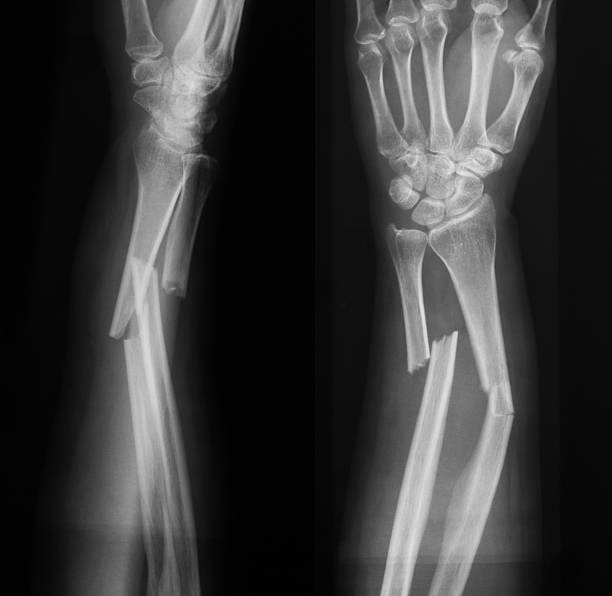

Onun sözlərinə görə, burada sınığın növündən və dövründən asılı olaraq plan dəyişir: “Sınıqlar zamanı təkcə sümük deyil, sümük zarı, damarlar və ətrafdakı yumuşaq toxumalar zədələnir.

Qan və limfa damarlarının yaralanması hemorragiya və ödəmə səbəb olur. Sınıqlar zamanı iltihabi dövr, bərpaedici dövr, remodeling dövr olur. Bu dövrlərdə də ona uyğun müalicə seçilir. Fizioterapevtik metodlardan elektroterapiya, ultrasəs, lazer ortezlər, su prosedurları, müalicəvi idman və s. tətbiq edilir”.